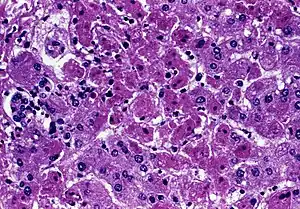

| Acute liver failure (with hepatocellular necrosis and sinusoidal bleeding) from Marburg virus, a rare cause | |

In the majority of acute liver failure (ALF) there is widespread hepatocellular necrosis beginning in the centrizonal distribution and progressing towards portal tracts. The degree of parenchymal inflammation is variable and is proportional to duration of disease.[6][19][20]

Zone 1 (periportal) occurs in phosphorus poisoning or eclampsia. Zone 2 (mid-zonal), although rare, is seen in yellow fever. Zone 3 (centrilobular) occurs with ischemic injury, toxic effects, carbon tetrachloride exposure, or chloroform ingestion. In acute acetaminophen overdose, toxification occurs, mostly in Zone III which has the highest level of P450 micro-enzymes. That fact along with Zone III's decreased oxygen level helps to explain why it is preferentially one of the initial sites of damage.